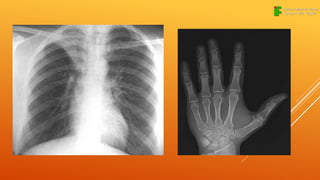

RADIOGRAFIA

A radiografia é uma imagem obtida, após

um feixe de raios X ou

raios gama, atravessa a região de estudo e

interagir com uma emulsão

fotográfica ou tela fluorescente, existe uma

grande variedade de tipos, tamanhos e

técnicas radiográficas.

Radiografia oral

Radiografia de tórax

Radiografia de membros

Radiografia de crânio

Radiografia de cérebro

Radiografia de coluna

RADIOGRAFIA A radiografia éuma imagem obtida, após um feixe de raios X ou raios gama, atravessa a região de estudo e interagir com uma emulsão fotográfica ou tela fluorescente, existe uma grande variedade de tipos, tamanhos e técnicas radiográficas.

Radiografia oral Radiografia detórax Radiografia de membros Radiografia de crânio Radiografia de cérebro Radiografia de coluna